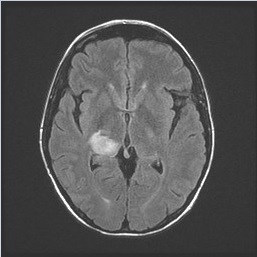

A 34-year-old woman presented to clinic on day 95 following allogeneic, myeloablative matched unrelated bone marrow transplantation with cyclophosphamide and total body irradiation conditioning for T-cell acute lymphoblastic leukemia. Transplantation had been complicated by pericardial effusion secondary to tacrolimus and by grade 1 graft-versus-host disease of the skin, both of which had resolved. She remained on sirolimus and prednisone 10 mg daily for immune suppression; she then developed sudden onset visual changes. A comprehensive eye examination noted no intraorbital pathology but demonstrated postchiasmal incongruous left hemianopsia. A brain MRI scan revealed a peripherally enhancing lesion centered in the right thalamus and subcentimeter enhancing lesions associated with petechial hemorrhage at the surface of the right superior colliculus and cerebellar vermis (Figure 1). Lumbar puncture was performed, but cerebrospinal fluid (CSF) analysis did not provide a diagnosis. The patient then underwent a brain biopsy with results below.